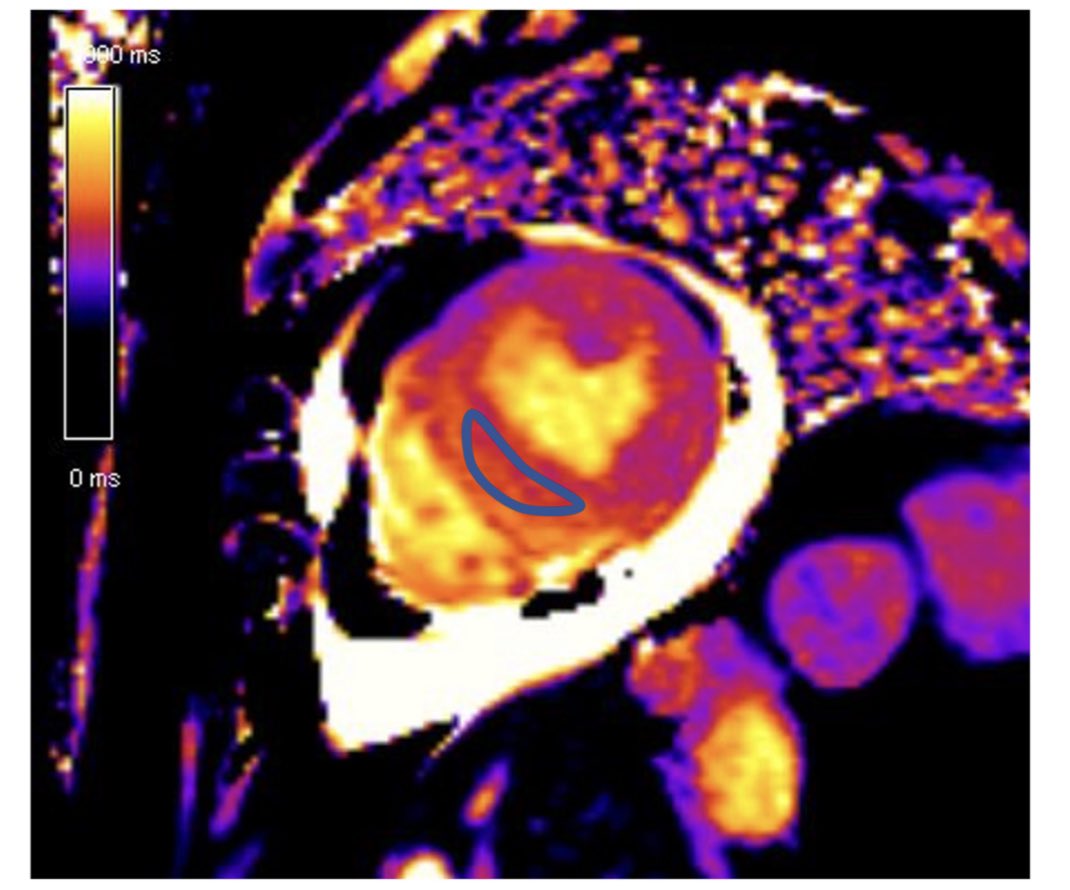

raised T1 and T2 mapping values

raised T1 and T2 mapping values

raised T1 and T2 mapping values

absence of LGE (at +5SD threshold) , but recent studies suggest LGE may be present  T1 and ECV mapping detect diffuse ECM abnormalities- here ECV normal at basal LV, increased at apical LV

T1 and ECV mapping detect diffuse ECM abnormalities- here ECV normal at basal LV, increased at apical LV strain can help detect myocardial deformation abnormalities

absence of LGE (at +5SD threshold) , but recent studies suggest LGE may be present  T1 and ECV mapping detect diffuse ECM abnormalities- here ECV normal at basal LV, increased at apical LV

T1 and ECV mapping detect diffuse ECM abnormalities- here ECV normal at basal LV, increased at apical LV strain can help detect myocardial deformation abnormalities